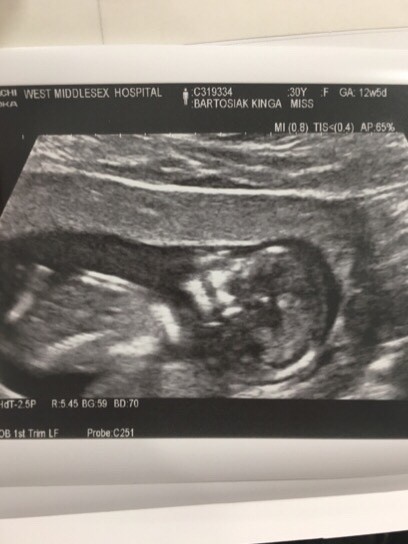

Dzisiaj wizyta mam nadzieję, że wszystko jest w porządku. Chciałabym już w końcu znać płeć dzidziusia by móc coś ładnego kupić :-]